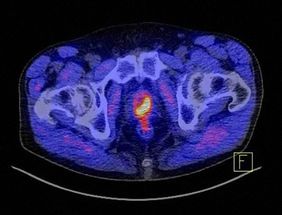

Mit dem PSA in Verbindung steht das Prostata-spezifische Membran Antigen (PSMA). Dieses Molekül ist auf der Oberfläche gesunder Prostatazellen vorhanden, sehr viel mehr aber auf Prostatakrebs-Zellen. Im restlichen Körper kommt das Protein kaum vor. „PSMA ist deshalb ein ideales Zielmolekül für die Diagnostik und zugleich auch für zielgerichtete Therapien von Prostatakrebs“, sagt Prof. Andreas Buck. Der Direktor der Klinik und Poliklinik für Nuklearmedizin des UKW wird beim Infotag der Frage nachgehen, ob ein PET-CT mit PSMA heute schon als Diagnosestandard bezeichnet werden kann.

Der 2. Patienteninformationstag des Prostatakrebszentrums des Uniklinikums Würzburg am 21. April 2018 trägt den Titel „Prostatakrebs: Vorsorge – Diagnostik – Therapie“. Die Abbildung zeigt, wie markant ein Prostatakarzinom unter Zuhilfenahme des Tracers PSMA im PET-CT als gelb-rotes Objekt dargestellt wird. Bild: Uniklinikum Würzburg